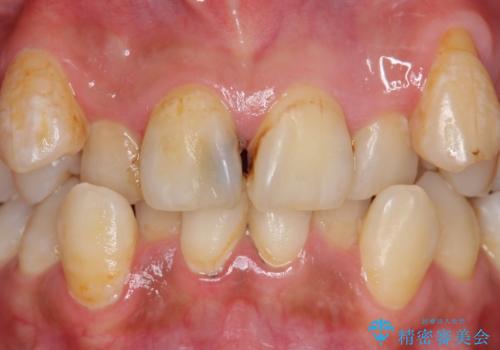

右上2は歯の神経が死んでおり、根尖病変を認めたため根管治療を行いました。

その後右上1,2番目及び左上1番目の歯に対してオールセラミッククラウンによる補綴を行いました。

今回用いたオールセラミッククラウンはジルコニアフレームという白い素材の上にセラミックを盛っているため、審美性が非常に高いのが特徴です。

また、ジルコニアは人工ダイヤモンドの材料にも使われているほど高い強度を持っており、そのためオールセラミッククラウンは審美性だけでなく、奥歯やブリッジの補綴も可能とするクラウンです。